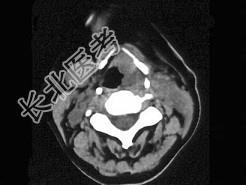

- 单项选择题女,54岁, 鼻咽部异物感约3个月,PE: 左侧声带固定,可见肿物, CT如图所示,应诊断为 ( )

B、喉癌